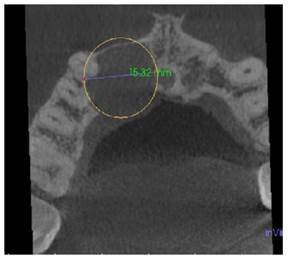

A la Tomografía computarizada de haz cónico (CBCT) se observó una imagen hipodensa que se extendía desde la pieza 1.1, 1.2, 1.3 hasta la pieza 1.4 extendiéndose principalmente hacia el paladar, en el cual se observa perdida de continuidad, las dimensiones de la lesión fueron de 14,38 mm en sentido longitudinal y 15,32 mm en sentido transversal (Figura 2a, b).

Figura 2b Tomografia corte coronal 03/07/2022. Imagen hipodensa de ancho 15,32 mm con pérdida de continuidad en la pared palatina a nivel de las piezas 1,1, 1,2, 13, y 14.